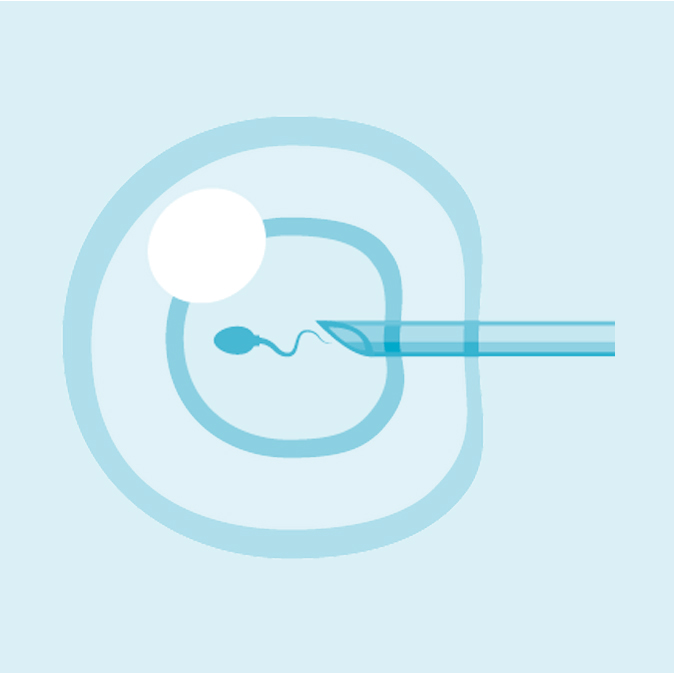

ICSI & IMSI

La référence

Nous mettons à la disposition de nos patients un bloc opératoire hautement équipé, dédié aux interventions de fertilité et aux techniques innovantes de chirurgie mini-invasive, garantissant précision, confort et récupération rapide. Notre laboratoire de biologie de la reproduction, doté d’équipements de pointe, assure toutes les étapes essentielles : fécondation in vitro (FIV), ICSI, congélation d’ovocytes et d’embryons, diagnostic embryonnaire, optimisation de la qualité ovocytaire et spermatique… Chaque procédure est réalisée selon les standards internationaux afin d’assurer les meilleures chances de réussite.